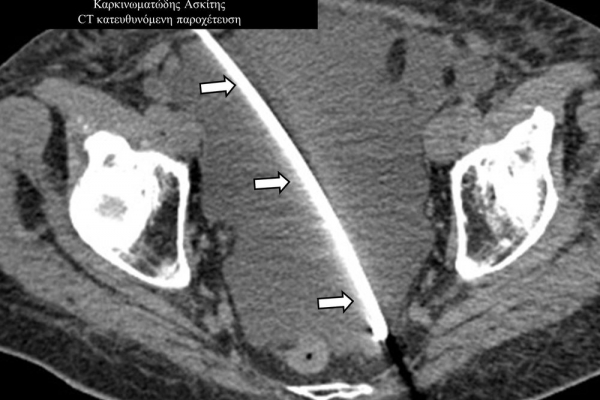

Οι απεικονιστικά καθοδηγούμενες διαδερμικές παροχετεύσεις είναι ελάχιστα επεμβατικές μέθοδοι εξωτερικής παροχέτευσης συμπτωματικών συλλογών, όπως ασκιτικές-καρκινικές-μετεγχειρητικές συλλογές, αποστήματα, πλευριτικές συλλογές-εμπυήματα.

Η διαδερμική παροχέτευση συλλογών συμβάλλει σημαντικά στην καλύτερη ποιότητα ζωής του ογκολογικού ασθενούς, αντιμετωπίζει τις οξείες τοξικές επιδράσεις στον οργανισμό που μπορούν να αποβούν θανατηφόρες, αλλά και επιτρέπει την απρόσκοπτη συνέχιση της θεραπείας του.

Η παρέμβαση διενεργείται υπό την καθοδήγηση αξονικού τομογράφου ή υπερήχων ή και με συνδυασμό τους. Ο επεμβατικός ακτινολόγος αρχικά αναισθητοποιεί την ανατομική περιοχή ενδιαφέροντος με τη χρήση τοπικής αναισθησίας και παρακεντεί την συλλογή διαδερμικά με λεπτή βελόνη. Στη συνέχεια μέσω ομοαξονικών συστημάτων συρμάτων-καθετήρων-διαστολέωντοποθετείται διαδερμικός καθετήρας τύπου pig-tail εντός της συλλογής, ο οποίος συνδέεται με εξωτερική παροχέτευση.